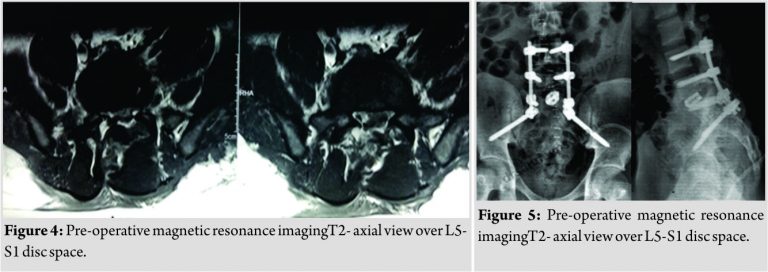

Magnetic resonance imaging (MRI) showed left L5-S1 root compression at foraminal level without signal changes at any other level (Fig. 3 and 4). He was operated on for reduction of translation, decompression, and stabilization. Biplanar instability was reduced with fixation using pedicular screws. L5 laminectomy was performed to decompress the roots, but both L5 and S1 roots were avulsed. Fixation was spanned from L4 to ilium. L5-S1transforaminal lumbar interbody fusion was performed using interbody cage and autologous iliac crest bone graft(Fig. 5).